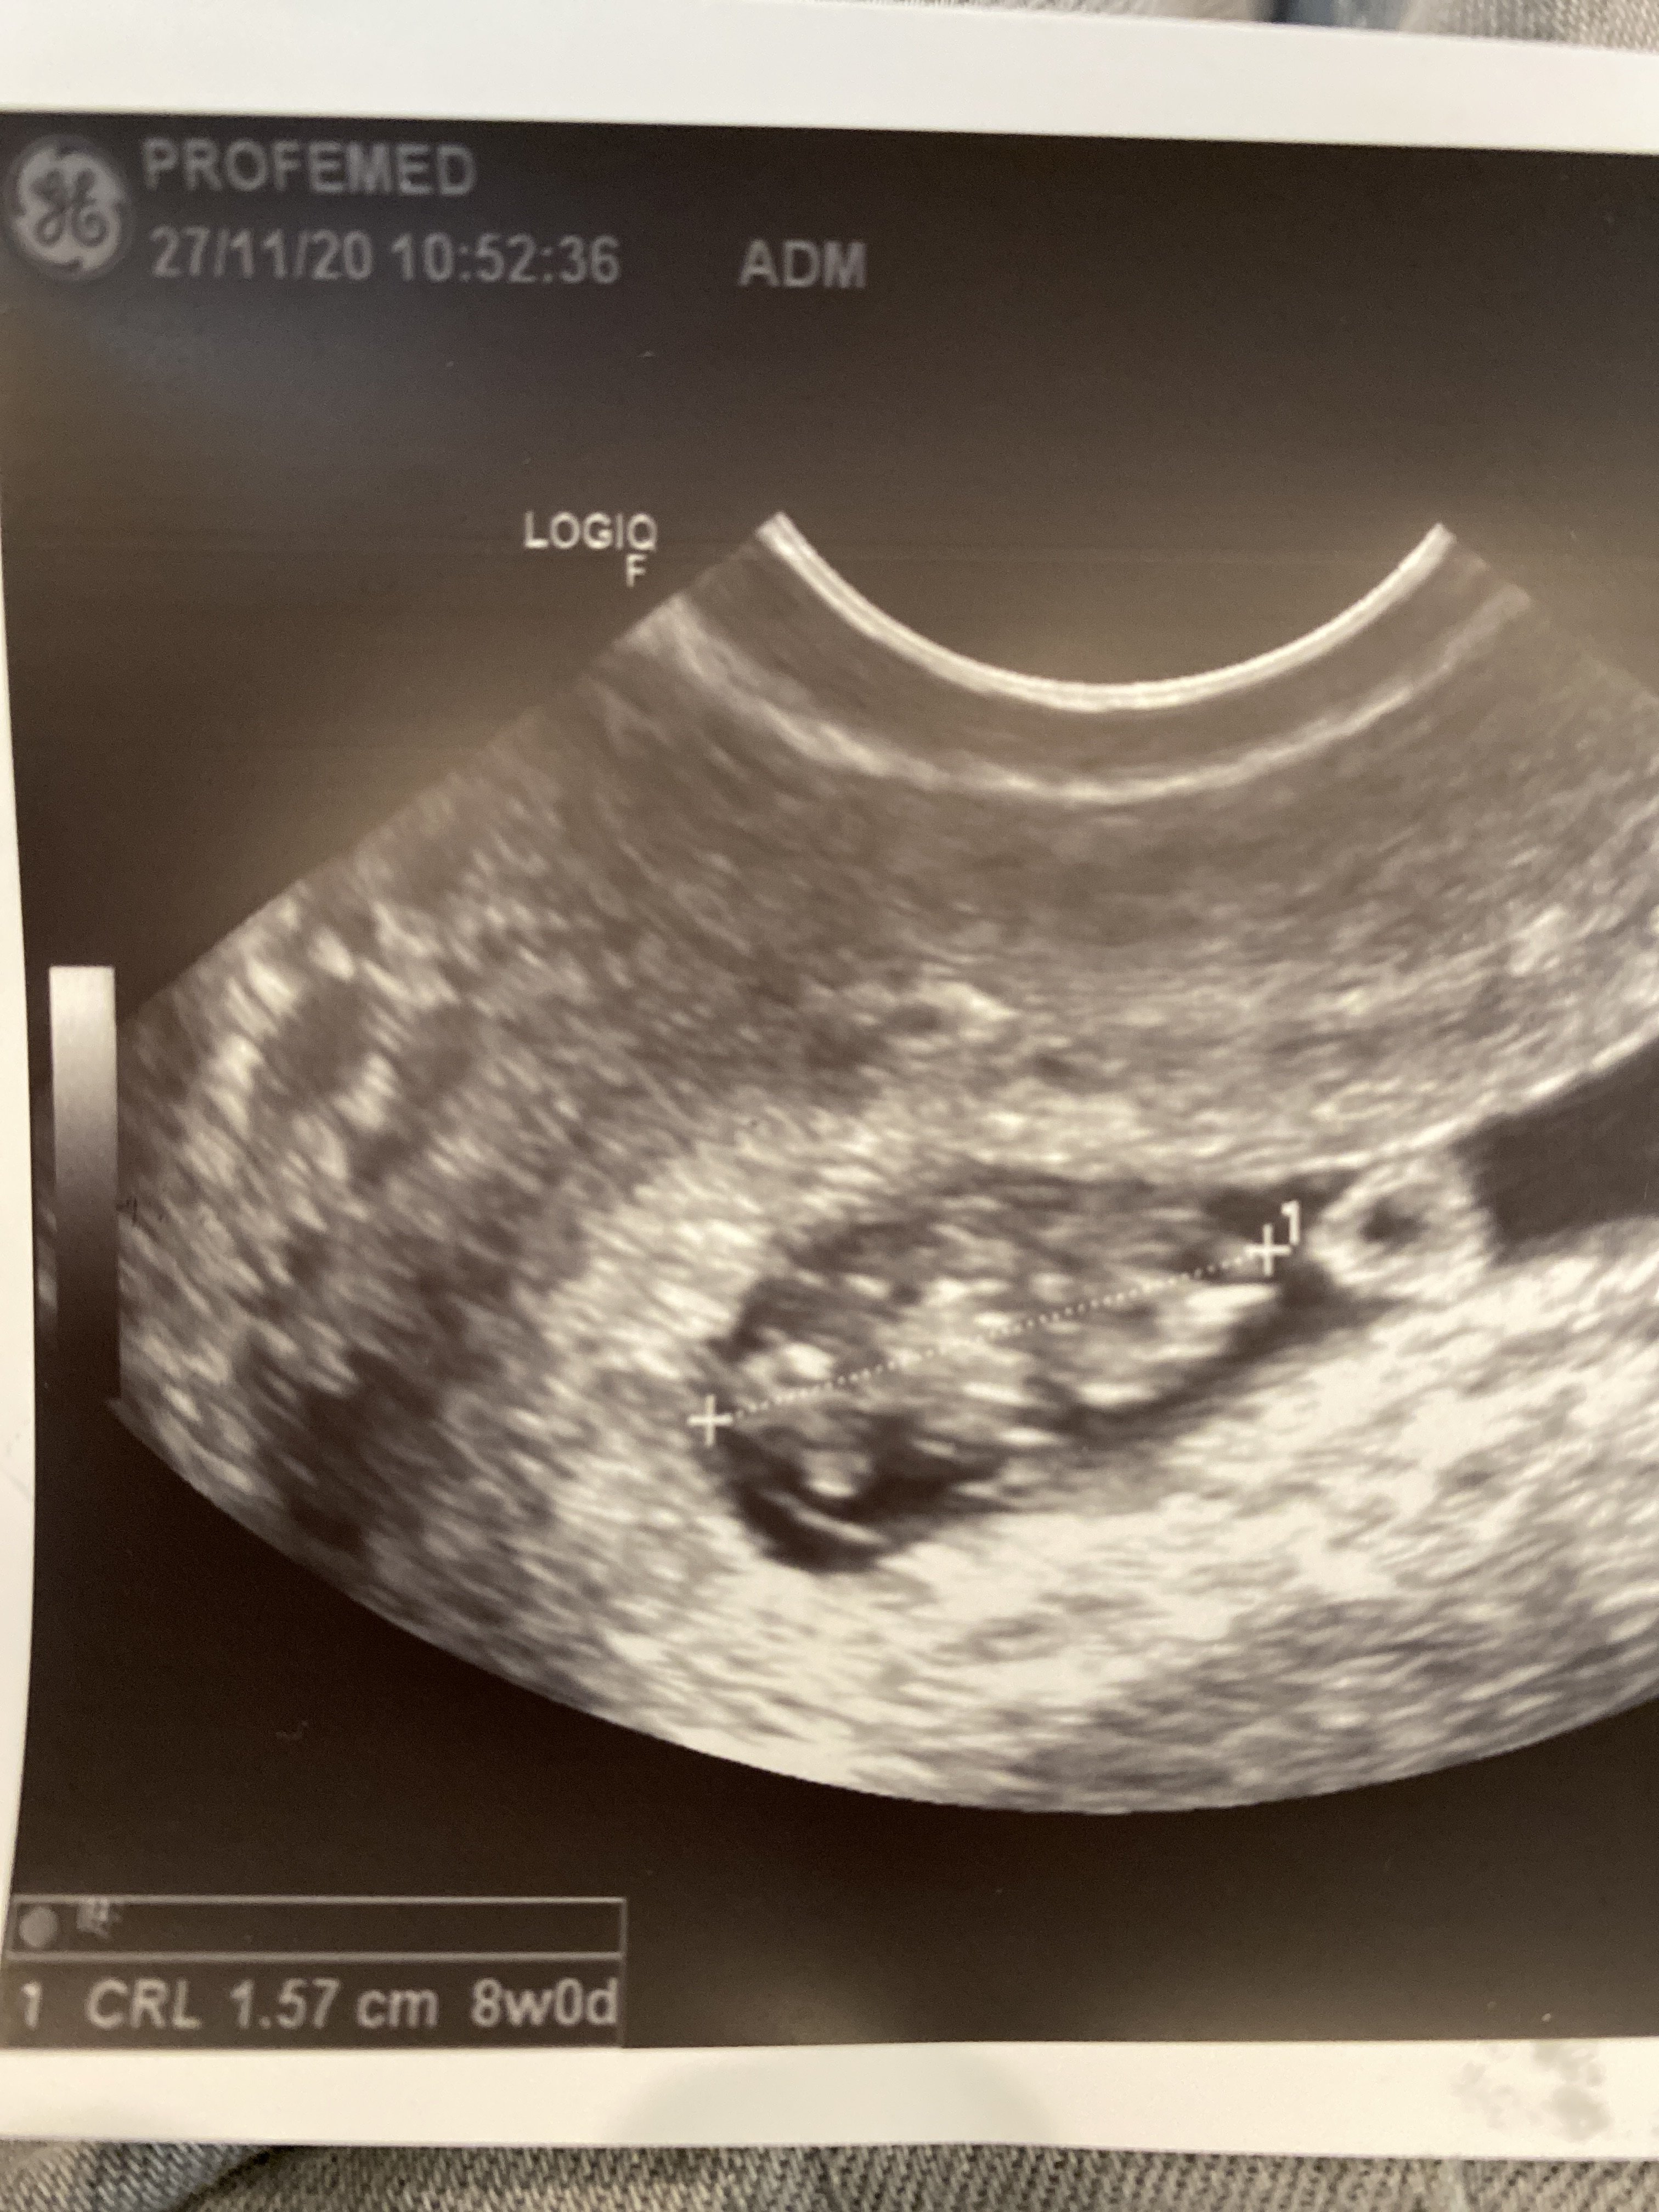

Dziewczyny jestem po wizycie :) maluszek ma już 1,57cm, serduszko pięknie bije i zaczynam się wreszcie cieszyć tą ciążą :D Przez wymioty Duphaston mi zamieniła na luteinę dopochwowo i założyła już kartę ciąży. Kolejna wizyta za 2 tygodnie.

Ja wg aplikacji flo mam 7+3 ale wg usg ciąża starsza i w karcie ciąży wpisany 8tydz.

Załączniki

• image.jpg

image.jpg

1,7 MB · Wyświetleń: 98